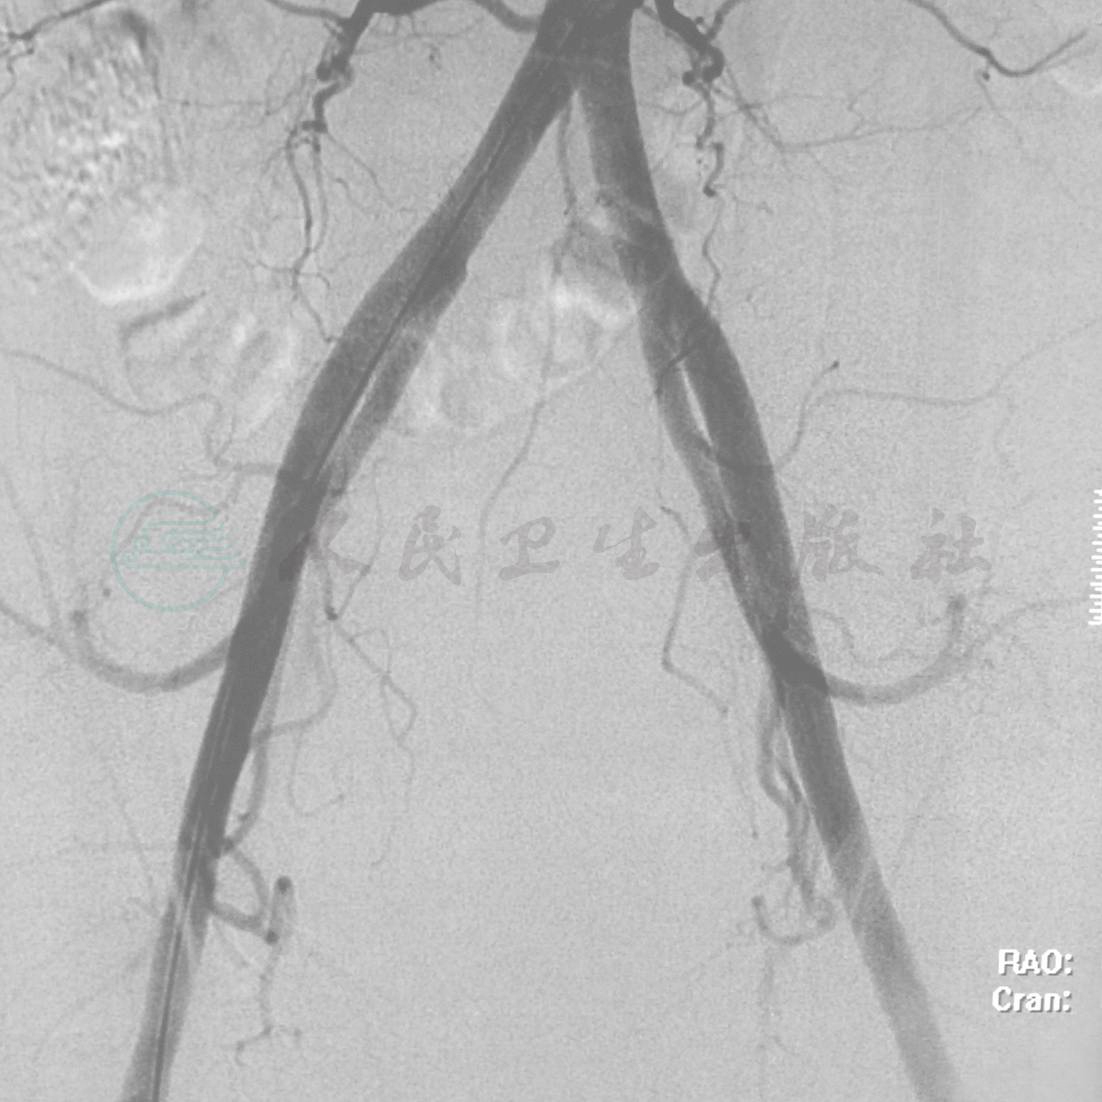

术前DSA肿瘤未见明确动脉供血(图5)。

图5 术前DSA肿瘤未见明确动脉供血